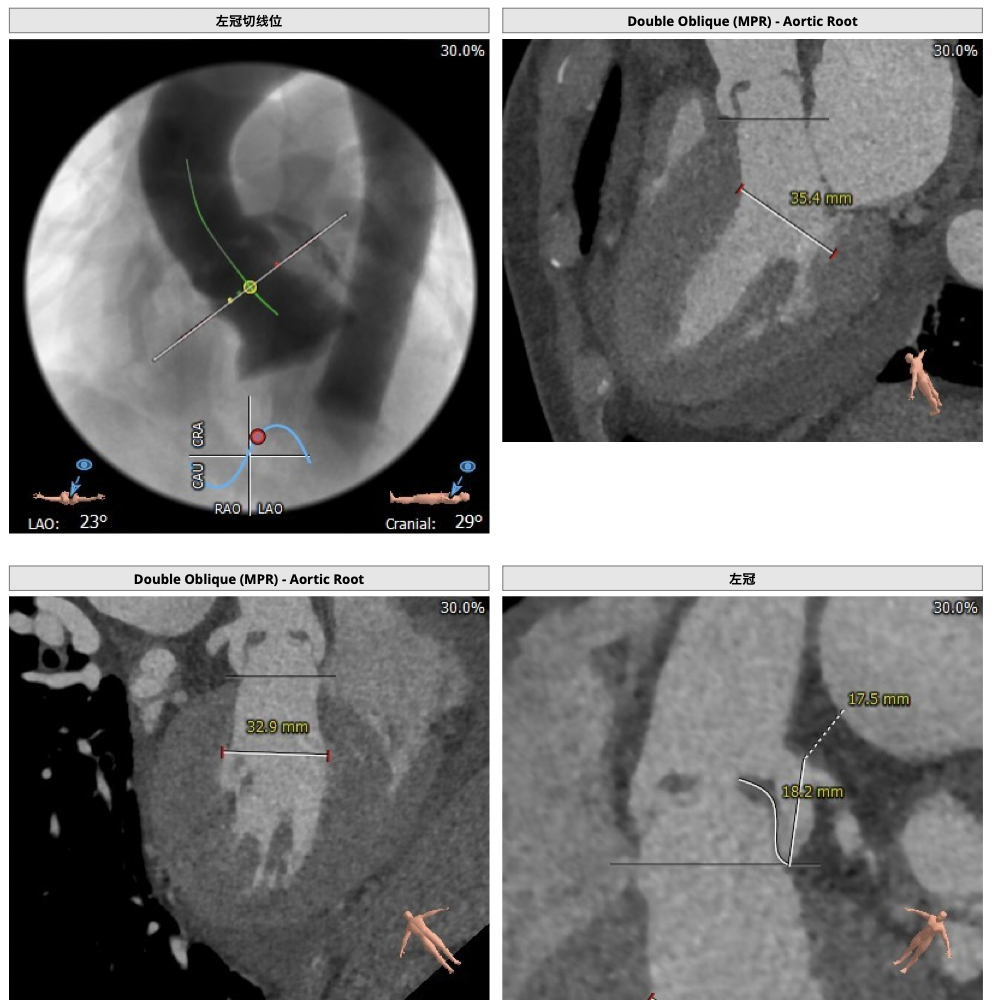

CT检查

确保冠脉安全,拟采取PCI+TAVR一站式手术策略,因患者右侧股动脉钙化严重、入路狭窄,拟采取无鞘法从右股动脉穿刺入路,选用20mm球囊预扩、L23号VenusA-Valve瓣膜、采用VenusA-Plus输送系统确保瓣膜的精确释放,瓣膜释放后结合造影和超声情况,决定是否后扩。